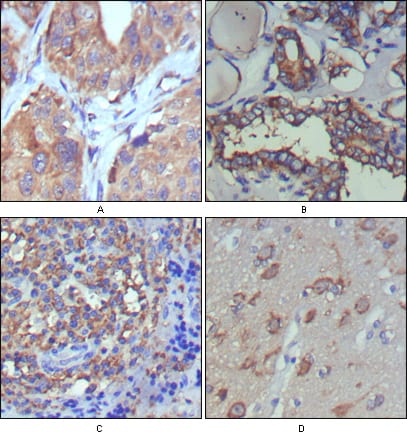

分类: 科研抗体货号: 20341别名: CD28LG; LAB7; B7.1应用: IHC,IF反应种属: Human

-